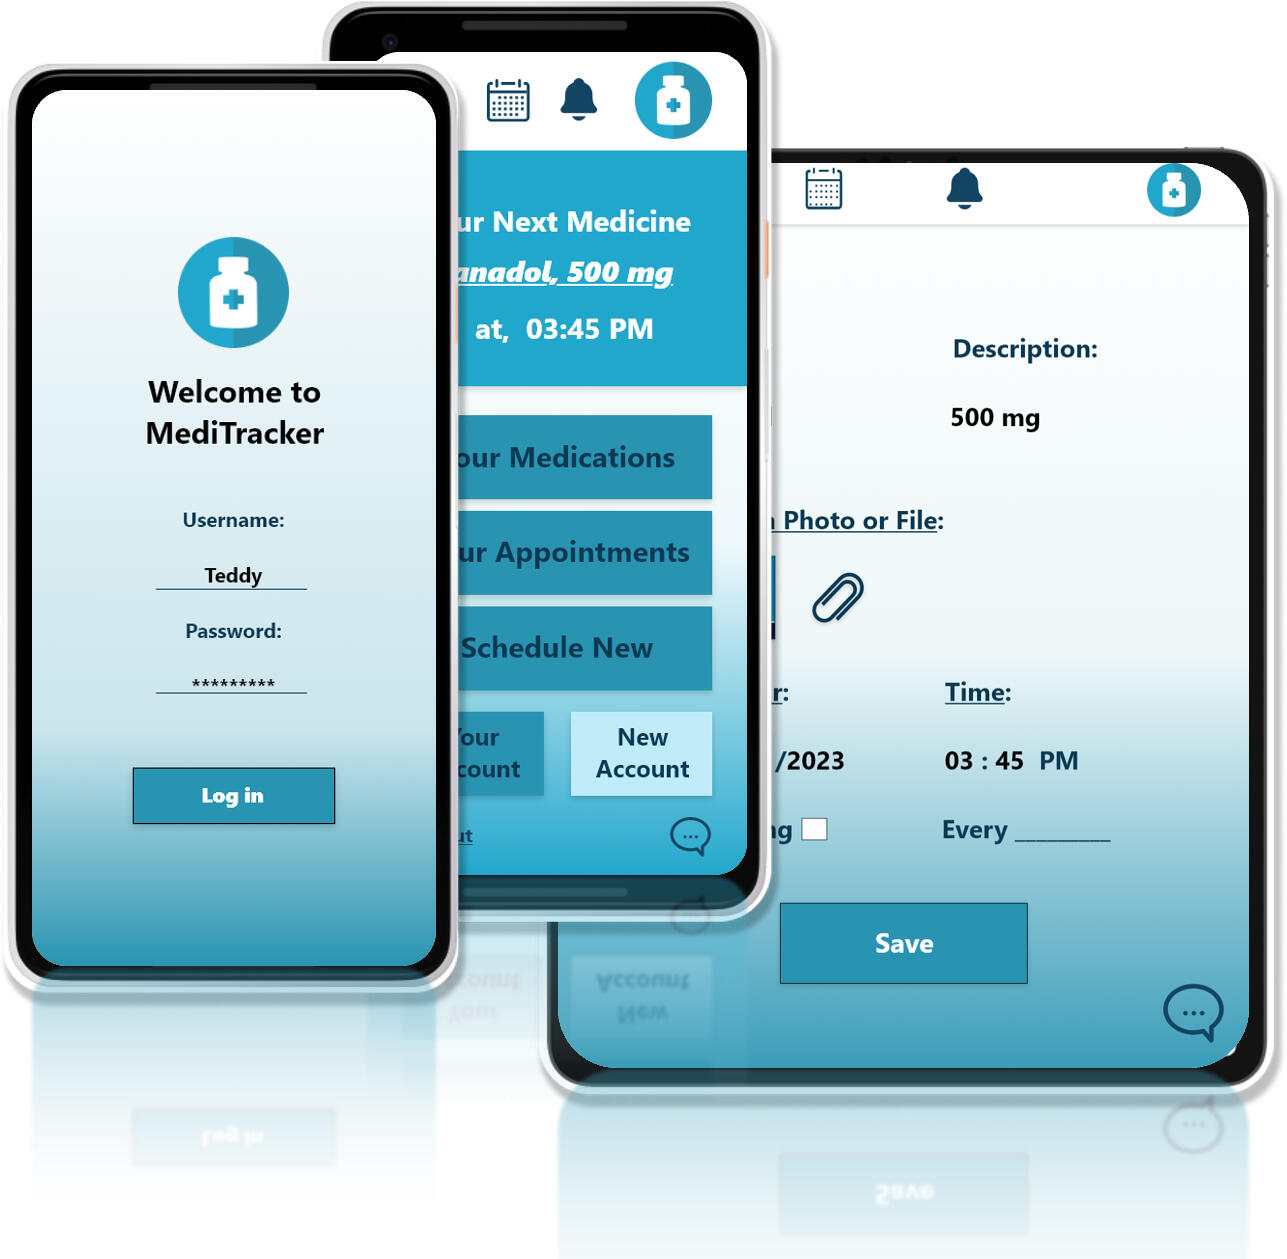

MediTracker:

A Responsive Web App for Medicine Management,

UX/UI Case Study

Project OverviewThis project focuses on evaluating the current iPay system to uncover usability issues and inefficiencies. The goal is to redesign the system into a more intuitive, user-friendly platform that meets users’ real needs and supports smoother task completion.Role: UX/UI Designer

Tools Used: Adobe XD / Photoshop, Microsoft Office

Project Type: Personal / Conceptual

Duration: 8 Weeks (2 Months)

Platform: Responsive Web (Mobile-First Approach)

Problem StatementMany people, especially the elderly and chronically ill, struggle to keep track of their medications.

Missed doses, double intakes, and medication confusion can lead to serious health complications.

GoalDesign a responsive web app that enables users to:

- Track their daily medications

- Set up reminders

- View dosage schedules

- Manage prescriptions easily

PrototypeDesigned low and high-fidelity prototypes using Adobe XD.Key Features:

- Medication Dashboard

- Add Medication (Name, Dosage, Time, Duration)

- Daily Reminder Notifications

- Prescription History

- Responsive Layout (Mobile, Tablet, Desktop)*********************🔗 View the Low-fidelity Prototype: Click here🔗 View the High-fidelity Prototype: Click here

TestUsability Study: FindingsA usability study was conducted to evaluate the functionality, accessibility, and overall user experience of the MediTracker prototype. Five participants were asked to perform common tasks such as signing up, setting medication reminders, and exploring app features.Key Findings:1. Security Matters

Users expressed the importance of securing their medical data. They appreciated having the option to log in with a username and password, which made them feel their personal health records were safe.2. Account Setup Needs Simplification

Some users found the account creation process slightly confusing or time-consuming. Clearer instructions and more intuitive input fields are needed to streamline onboarding.3. Desire for a Centralized Notification Area

Users liked having a dedicated notification space where they could view alerts about medications and doctor appointments. This feature helped them feel more organized and in control.MockupsBased on the insights gathered from the usability study, several key design improvements were implemented to enhance the user experience:- Notification Area:

A dedicated notification section was added, allowing users to easily view alerts for upcoming medications and doctor appointments. This helps users stay organized and ensures they don’t miss important tasks.- Login & Logout Functionality:

To address user concerns around data privacy and security, login and logout buttons were introduced. This ensures that personal health records are protected and only accessible to the user.These updates were reflected in the high-fidelity mockups for both mobile and desktop versions of the app.

Responsive DesignAdopted a mobile-first approach and expanded to tablet and desktop screens.Focused on:

- Touch-friendly UI for phones

- Optimized font sizes and buttons

- Consistent experience across devices*********************📱 Mobile: Click here to view

📲 Tablet: Click here to view